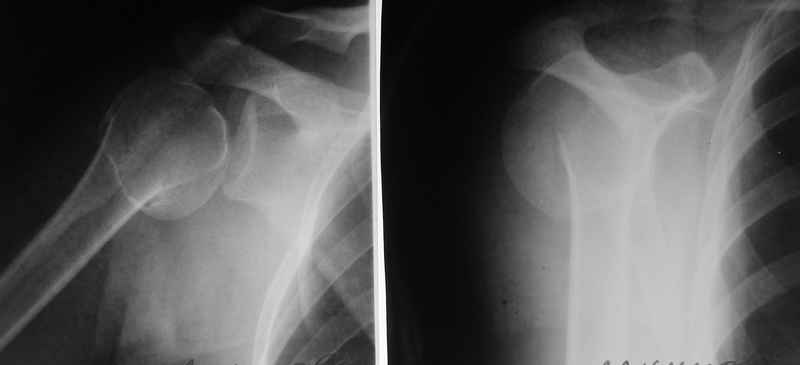

Женщина, 33 г., упала неделю назад. Сейчас в гипсовой шине. Перелом шейки плеча. Снимок в приложении.

Боковой снимок нормально не сделать, вторая проекция сделана под углом 30 градусов. На 3D реконструкции смещение видно лучше. Плечо сейчас во внутренней ротации. То есть на снимке, который по лопатке - фас, плечо свидно с латеральной стороны. Где лопатка в профиль - плечо вид сзади фас. То есть перелом вколоченный, с варусом градусов 45.

И последний снимок - "репозиция".

Мнения у нас разошлись - есть сторонники оставить как есть, подержать в гипсе, и начать разработку. Другие полагают, что такое смещение надо устранить.

Как полагаете, надо ли здесь что-то менять? Или и так приемлемо? Если вправлять, то как? Чем фиксировать? Спасибо!